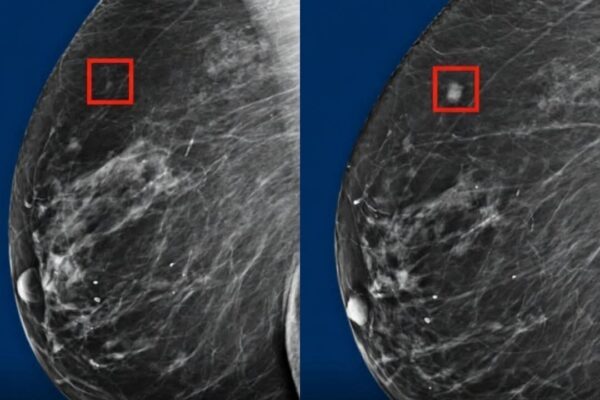

New AI Detects Breast Cancer up to 5 Years Before it Develops

Revolution in Breast Cancer Prevention: AI System Detects Risk Up to Five Years in Advance Key Takeaways: •Newly Invented Artificial Intelligence Can Detect Breast Cancer Many Years before it surfaces…